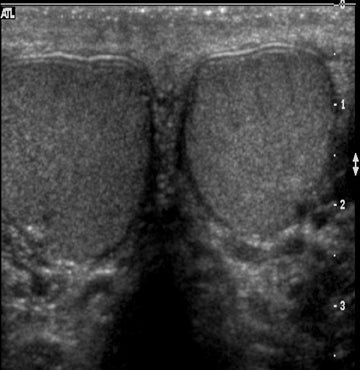

High-resolution digital imaging for detailed cellular analysis.